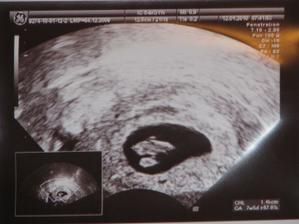

Naše dlho očakávané...